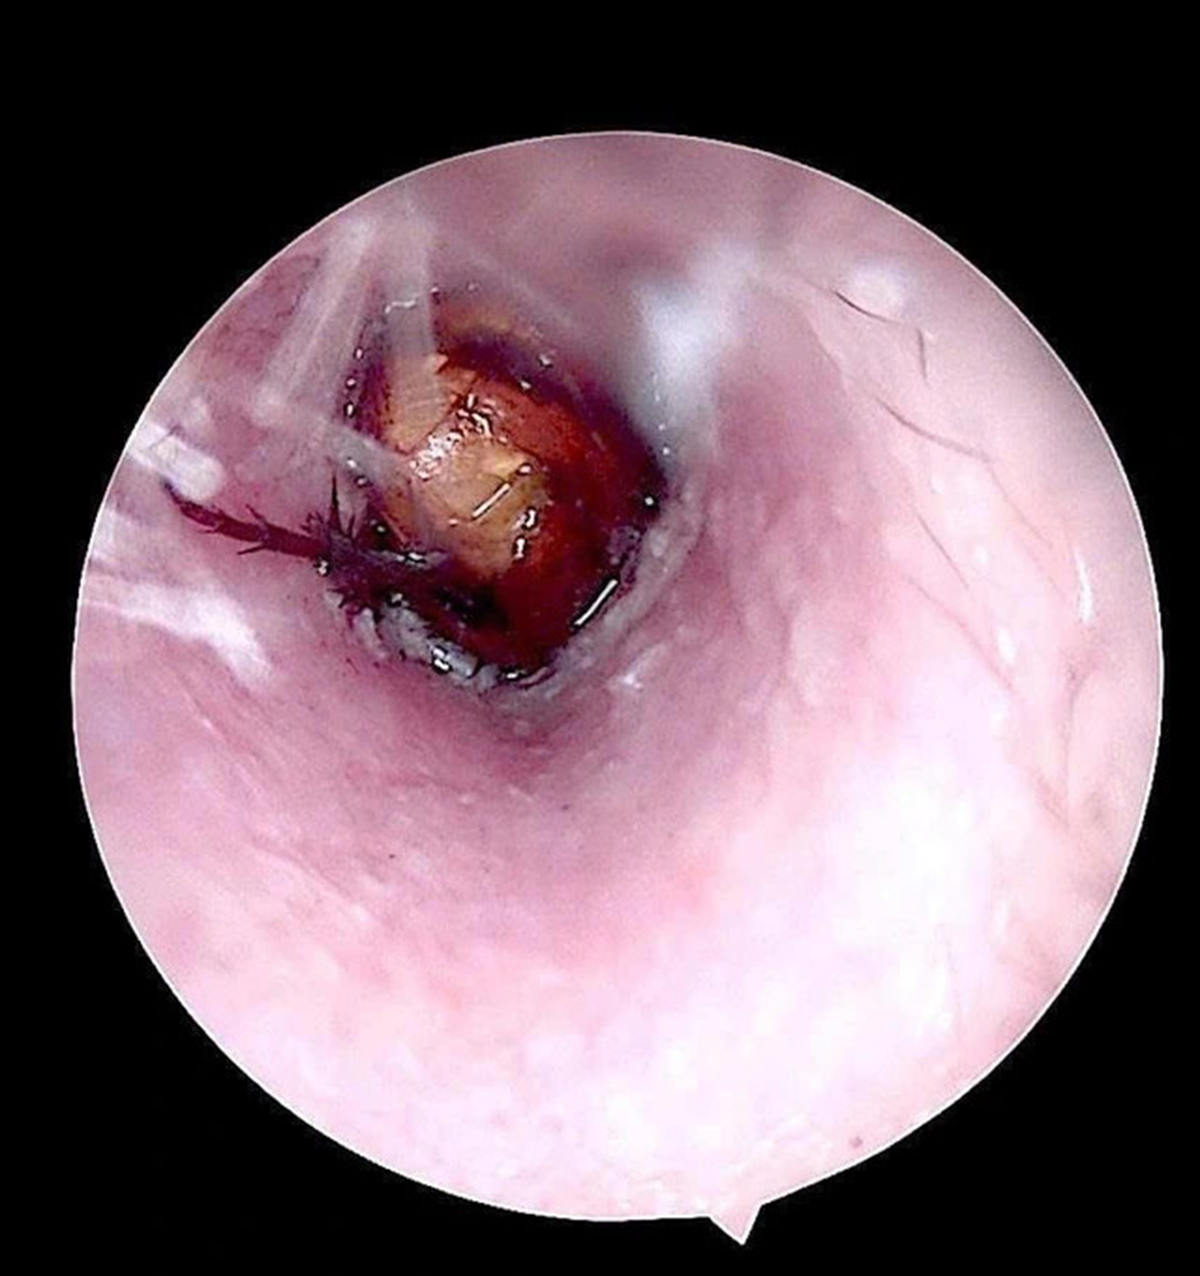

Tại viện qua kiểm tra, bác sĩ ghi nhận ống tai ngoài bên phải của bệnh nhân có hiện tượng xung huyết, có dị vật sống. Các bác sĩ đã tiến hành nội soi, gắp dị vật là một con côn trùng có kích thước khoảng 1,5cm.

Kiểm tra sau lấy dị vật, phát hiện màng nhĩ bệnh nhân nề đỏ do phản ứng viêm và kích thích trong quá trình tự lấy dị vật.

Hình ảnh côn trùng sống trong ống tai của bệnh nhân.